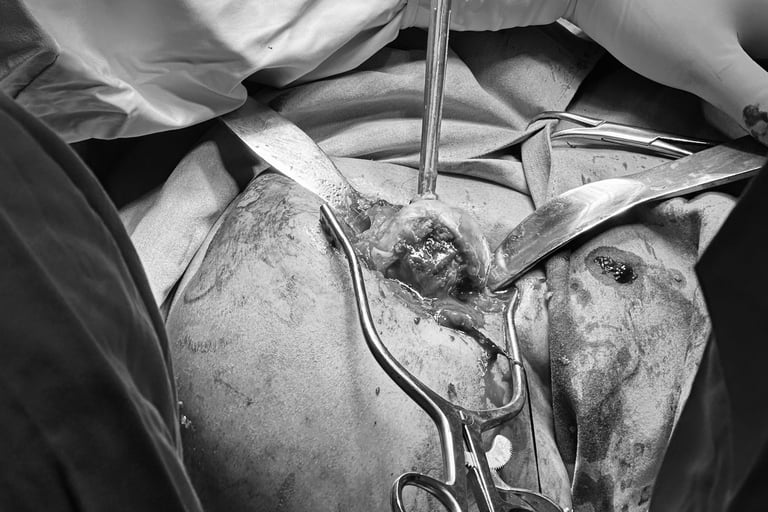

Tenodesis blanda del bíceps en prótesis reversa de hombro.

Preparación de húmero en prótesis reversa de hombro

Preparación de canal medular de húmero en prótesis reversa de hombro, guía de alineación con antebrazo.

Colocación de vástago de húmero en prótesis reversa de hombro

Dr. Manuel Martínez Domínguez colocando prótesis de hombro